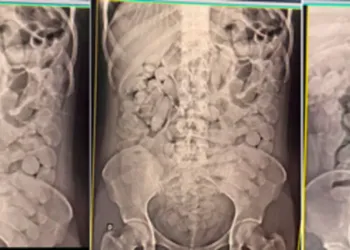

Uma criança de 2 anos foi internada no Centro de Terapia Intensiva (CTI) da Santa Casa de Campo Grande, na ...